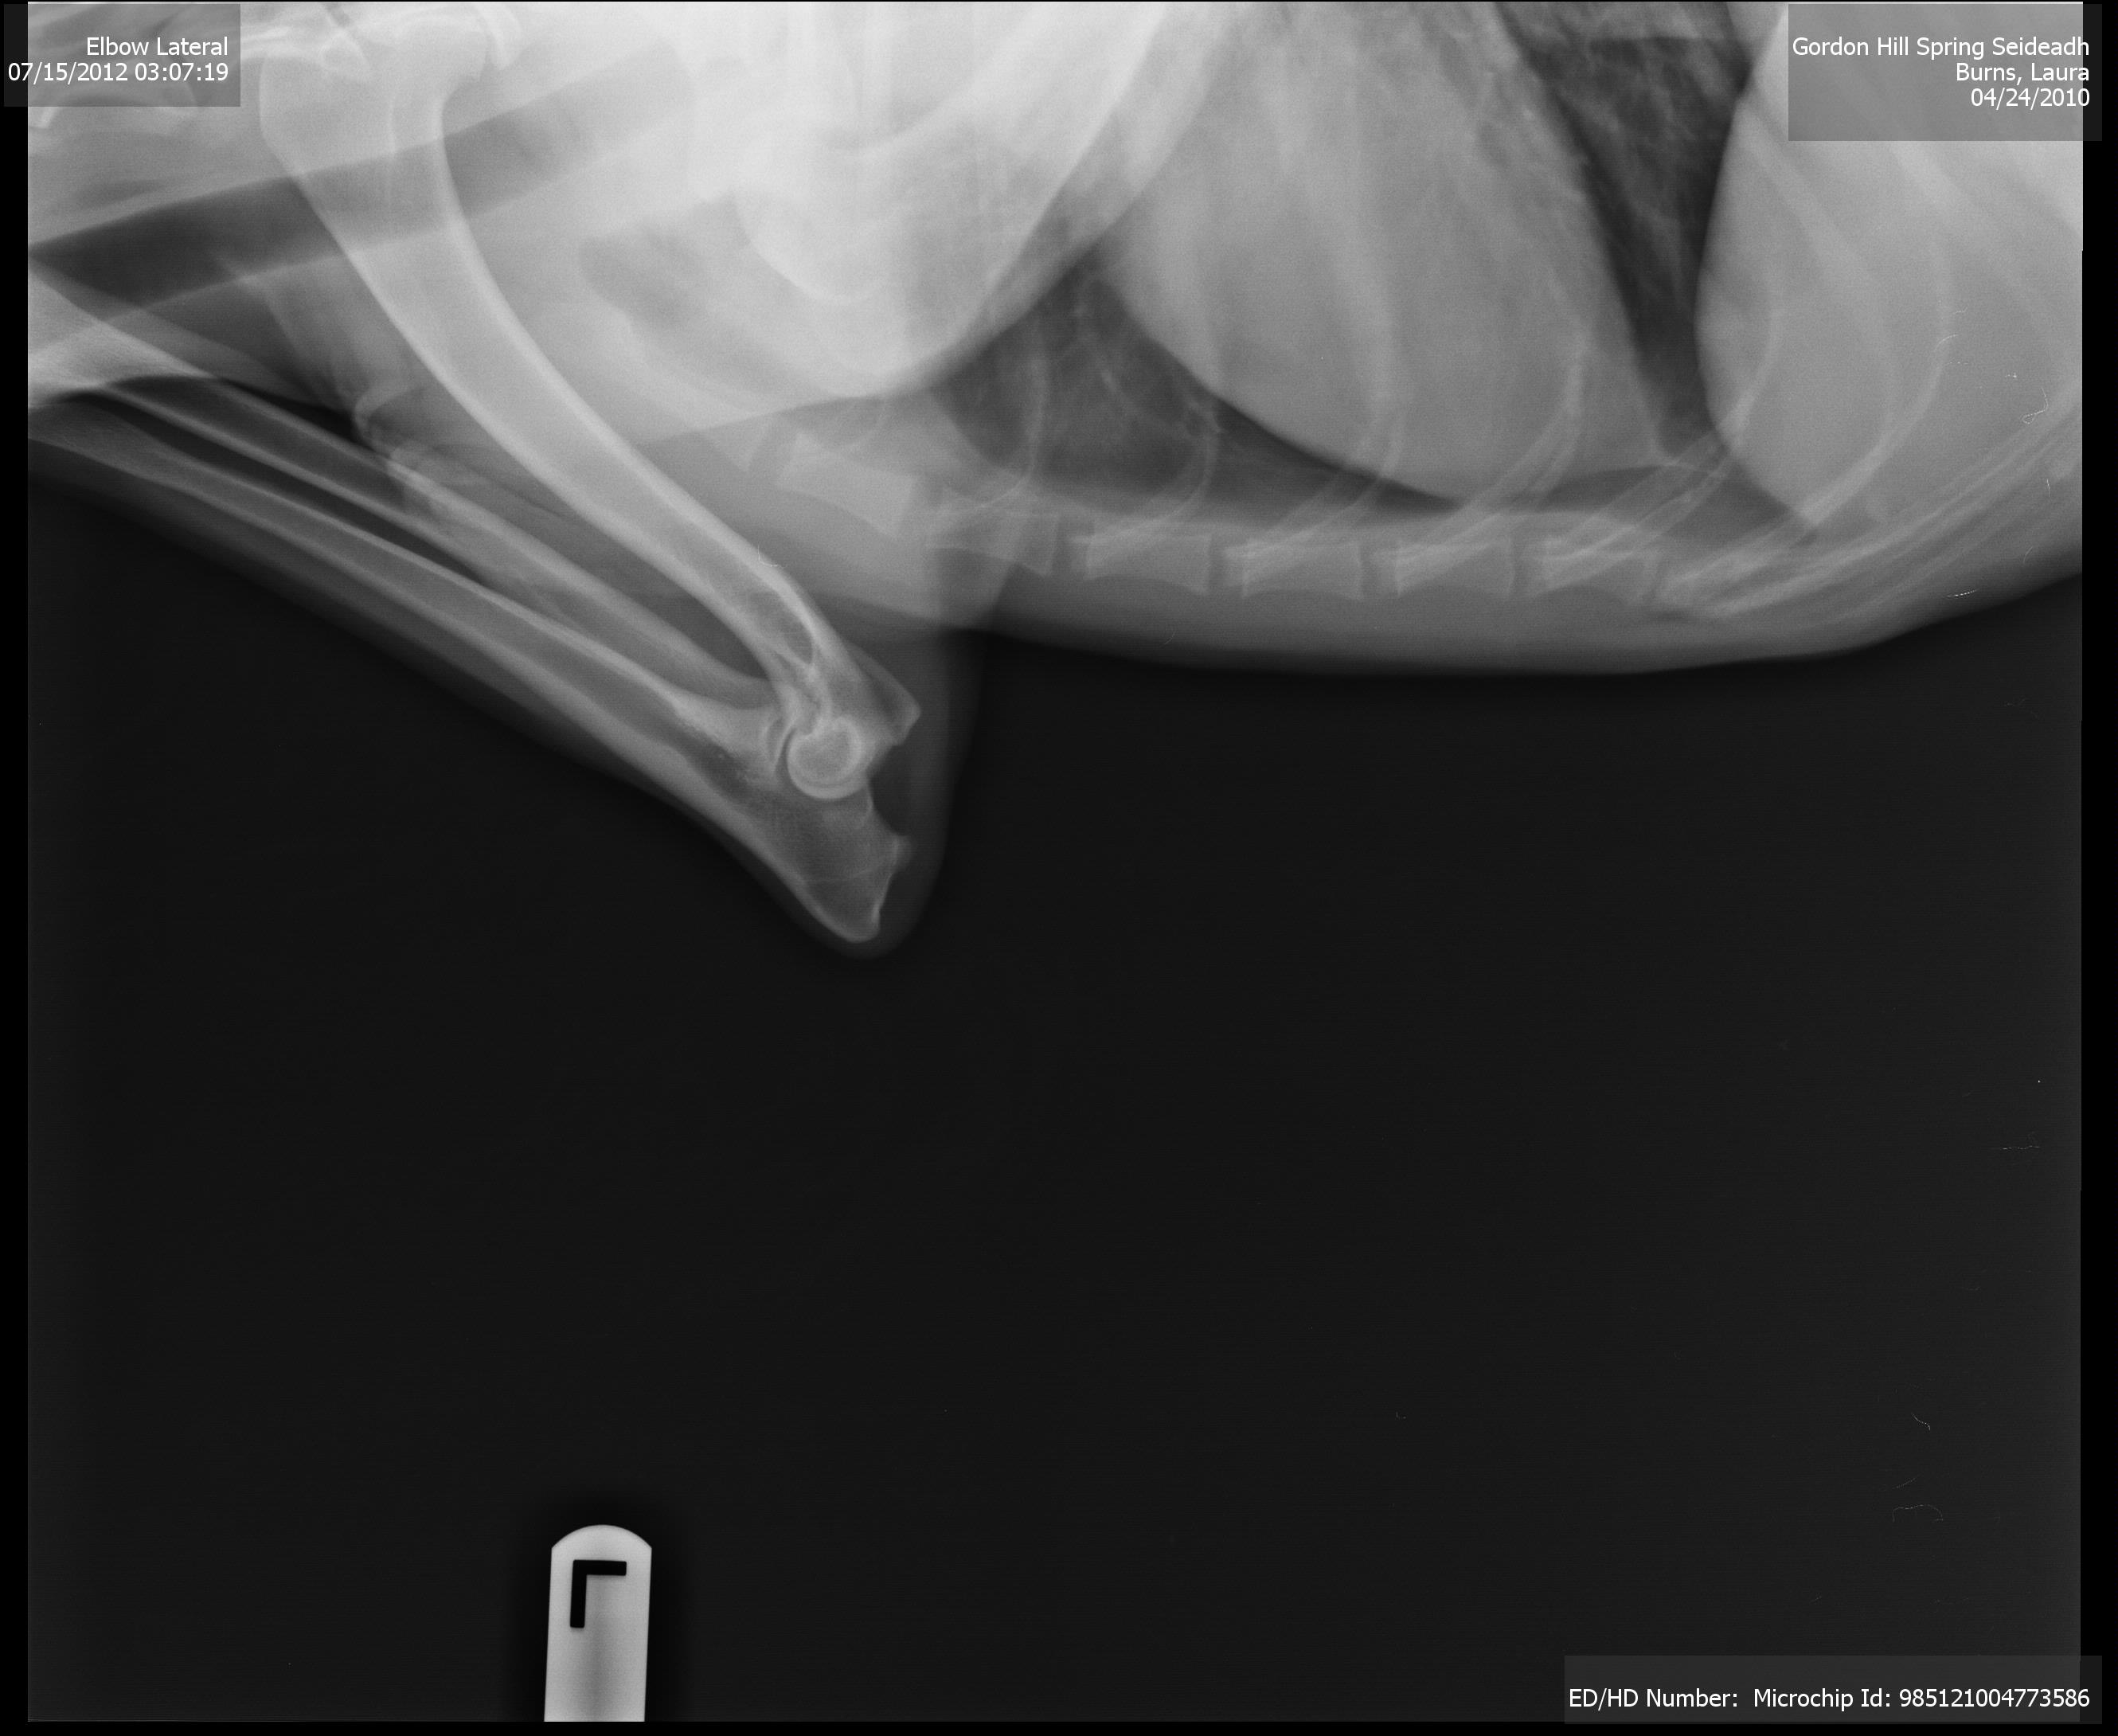

These hips look good! I don’t know everything to look for, but I see deep, tight sockets with no signs of arthritis or other “bony changes.” They look great to me, with my layperson’s eye, and the vet agreed. Here is one of her elbow x-rays, although I have less of an idea of what to look for here:

Now we wait for OFA (Orthopedic Foundation for Animals) to have their say. But no matter what, I’m assured I have a sound animal, capable of many years of activity, at least as far as her skeleton is concerned. Dr. Ericson and his staff at Companion Veterinary Clinic do a super job!